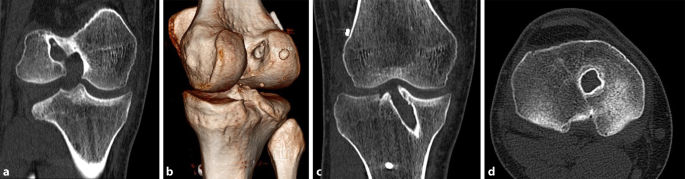

Kahnbeinpseudarthrose Handchirurgie Dresden

Kahnbein Pseudarthrose

Kahnbeinpseudarthrose